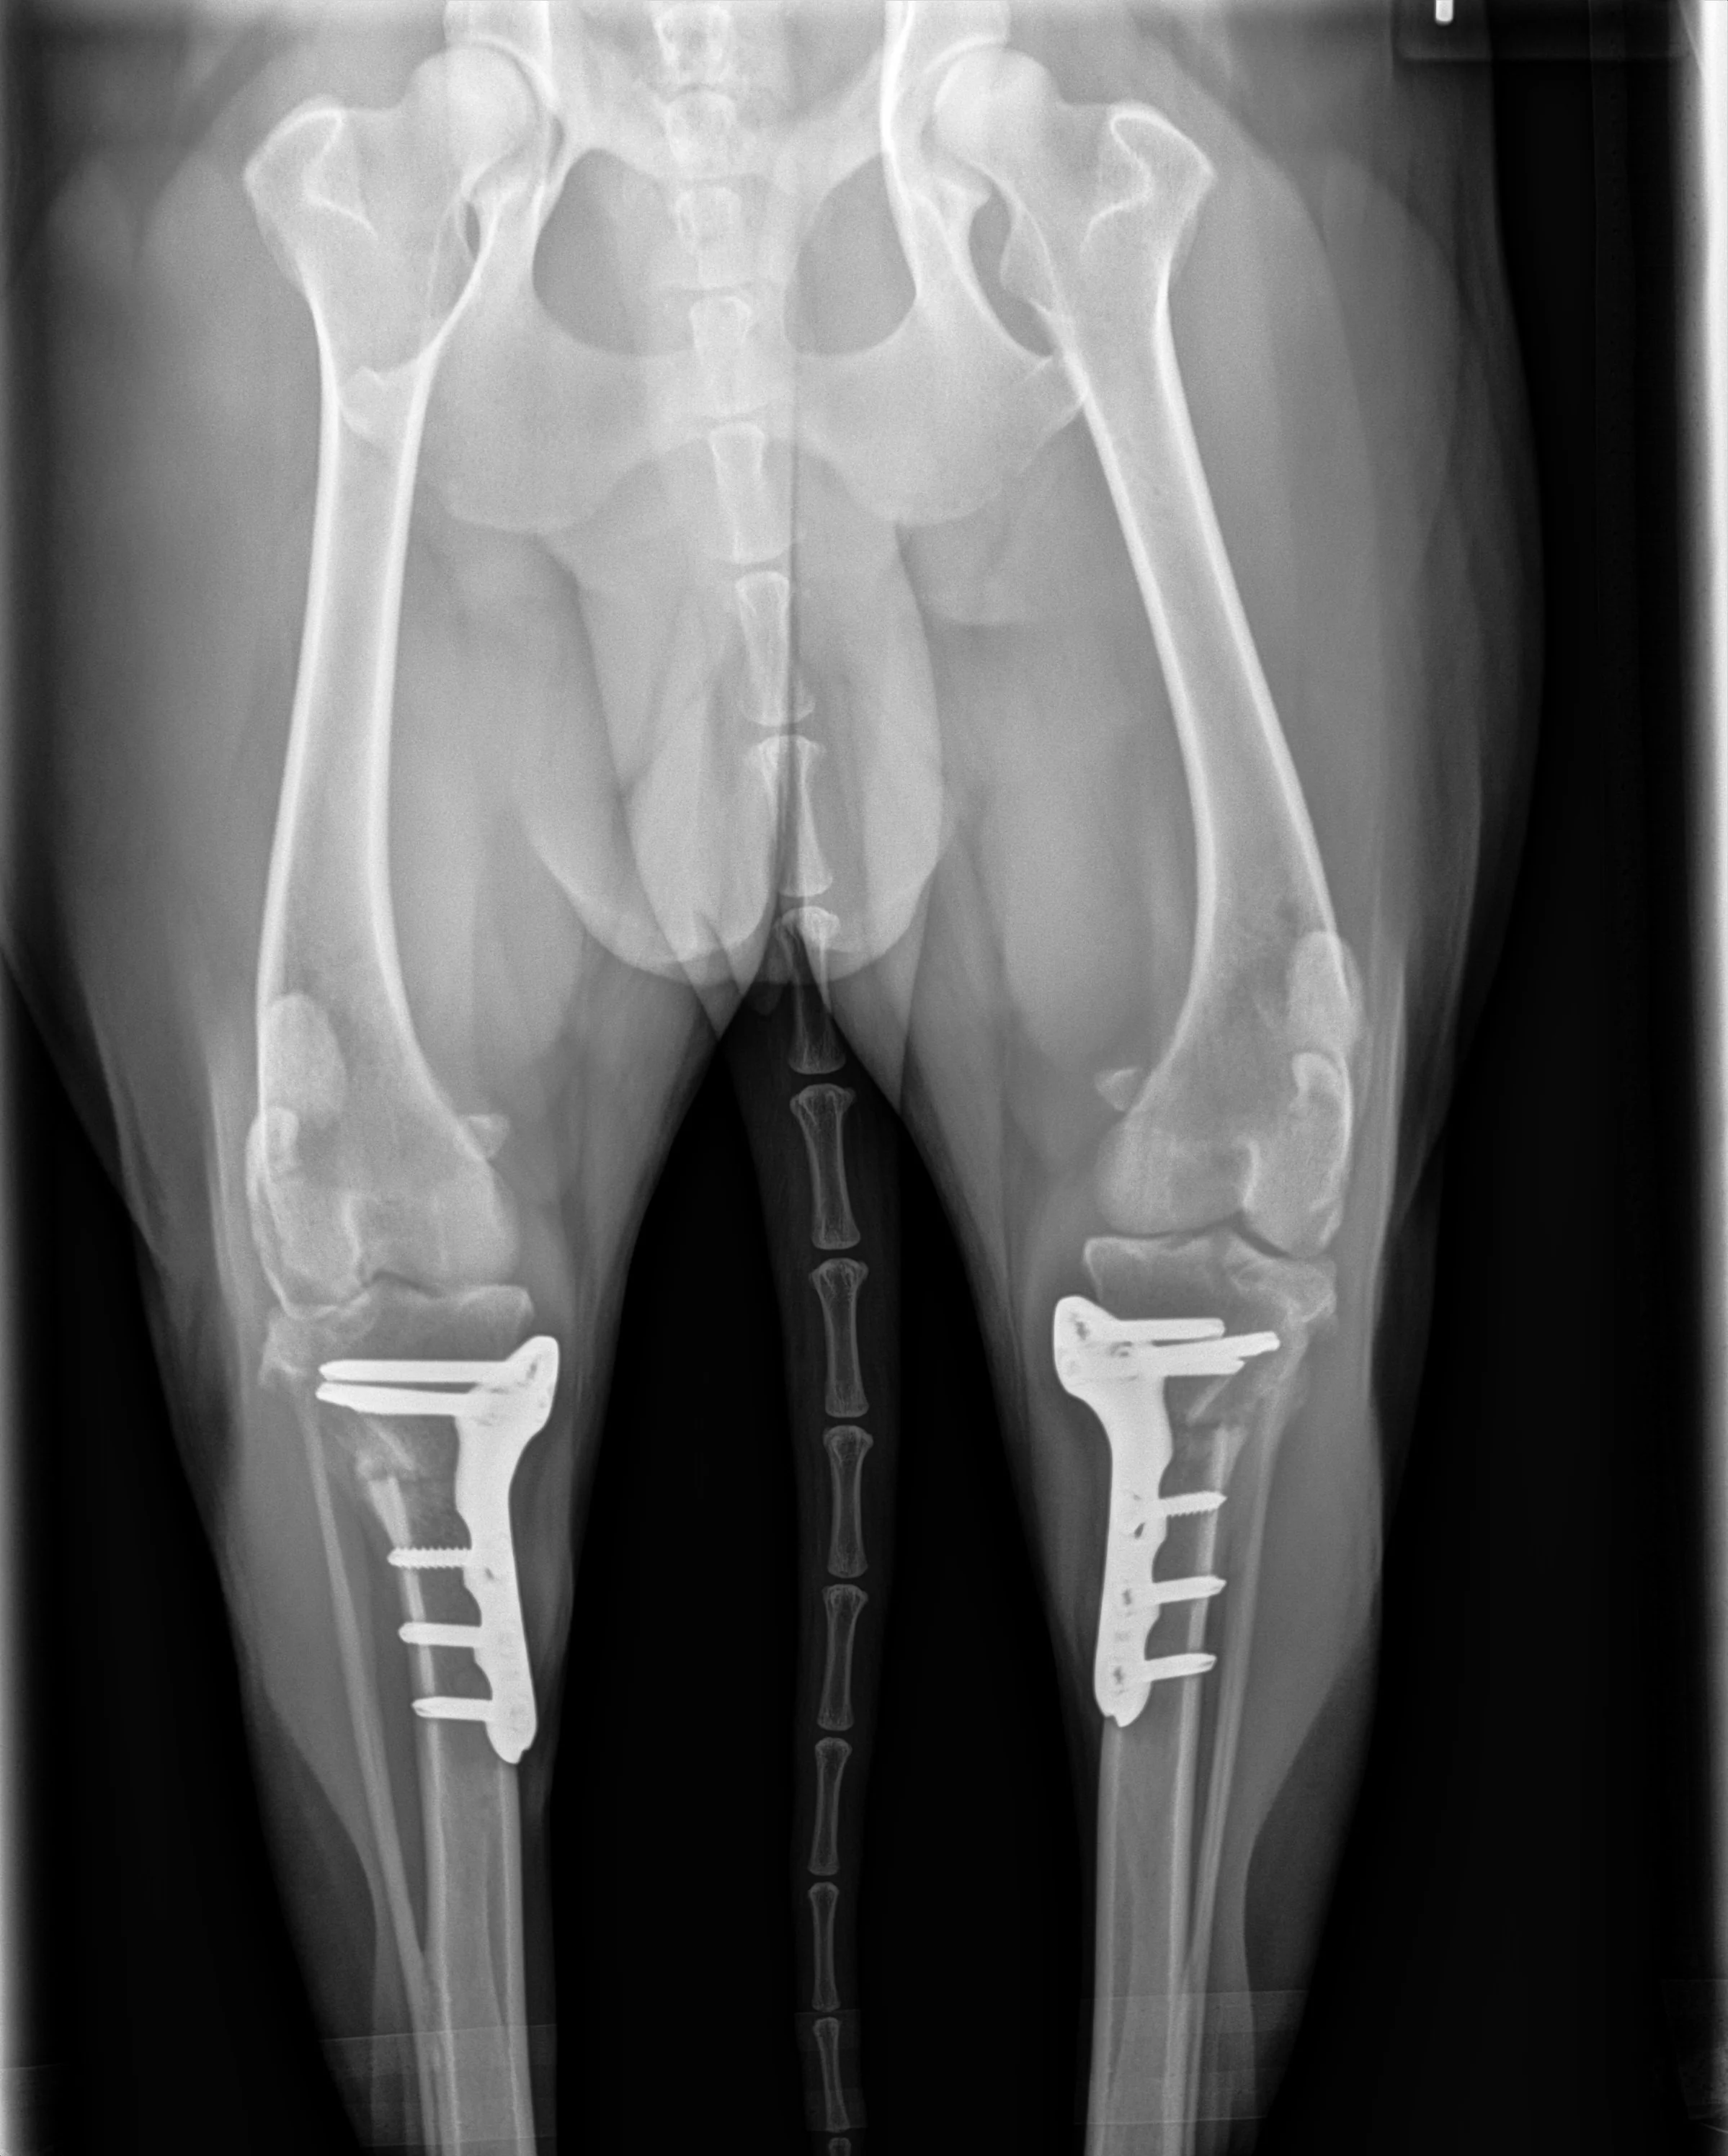

I know firsthand how challenging this can be! Lily had bilateral TPLOs (surgical repair of both of her cranial cruciate ligaments) done in October 2025 by Dr. Travis Reed. The surgery went smoothly, but she still required eight weeks of strict activity restriction and another eight weeks of very gradual return to activity.